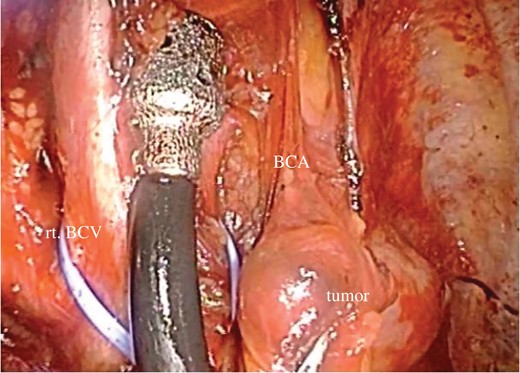

Chest CT (A) and MRI (B) revealed a mediastinal nodule adjoining the BCA.